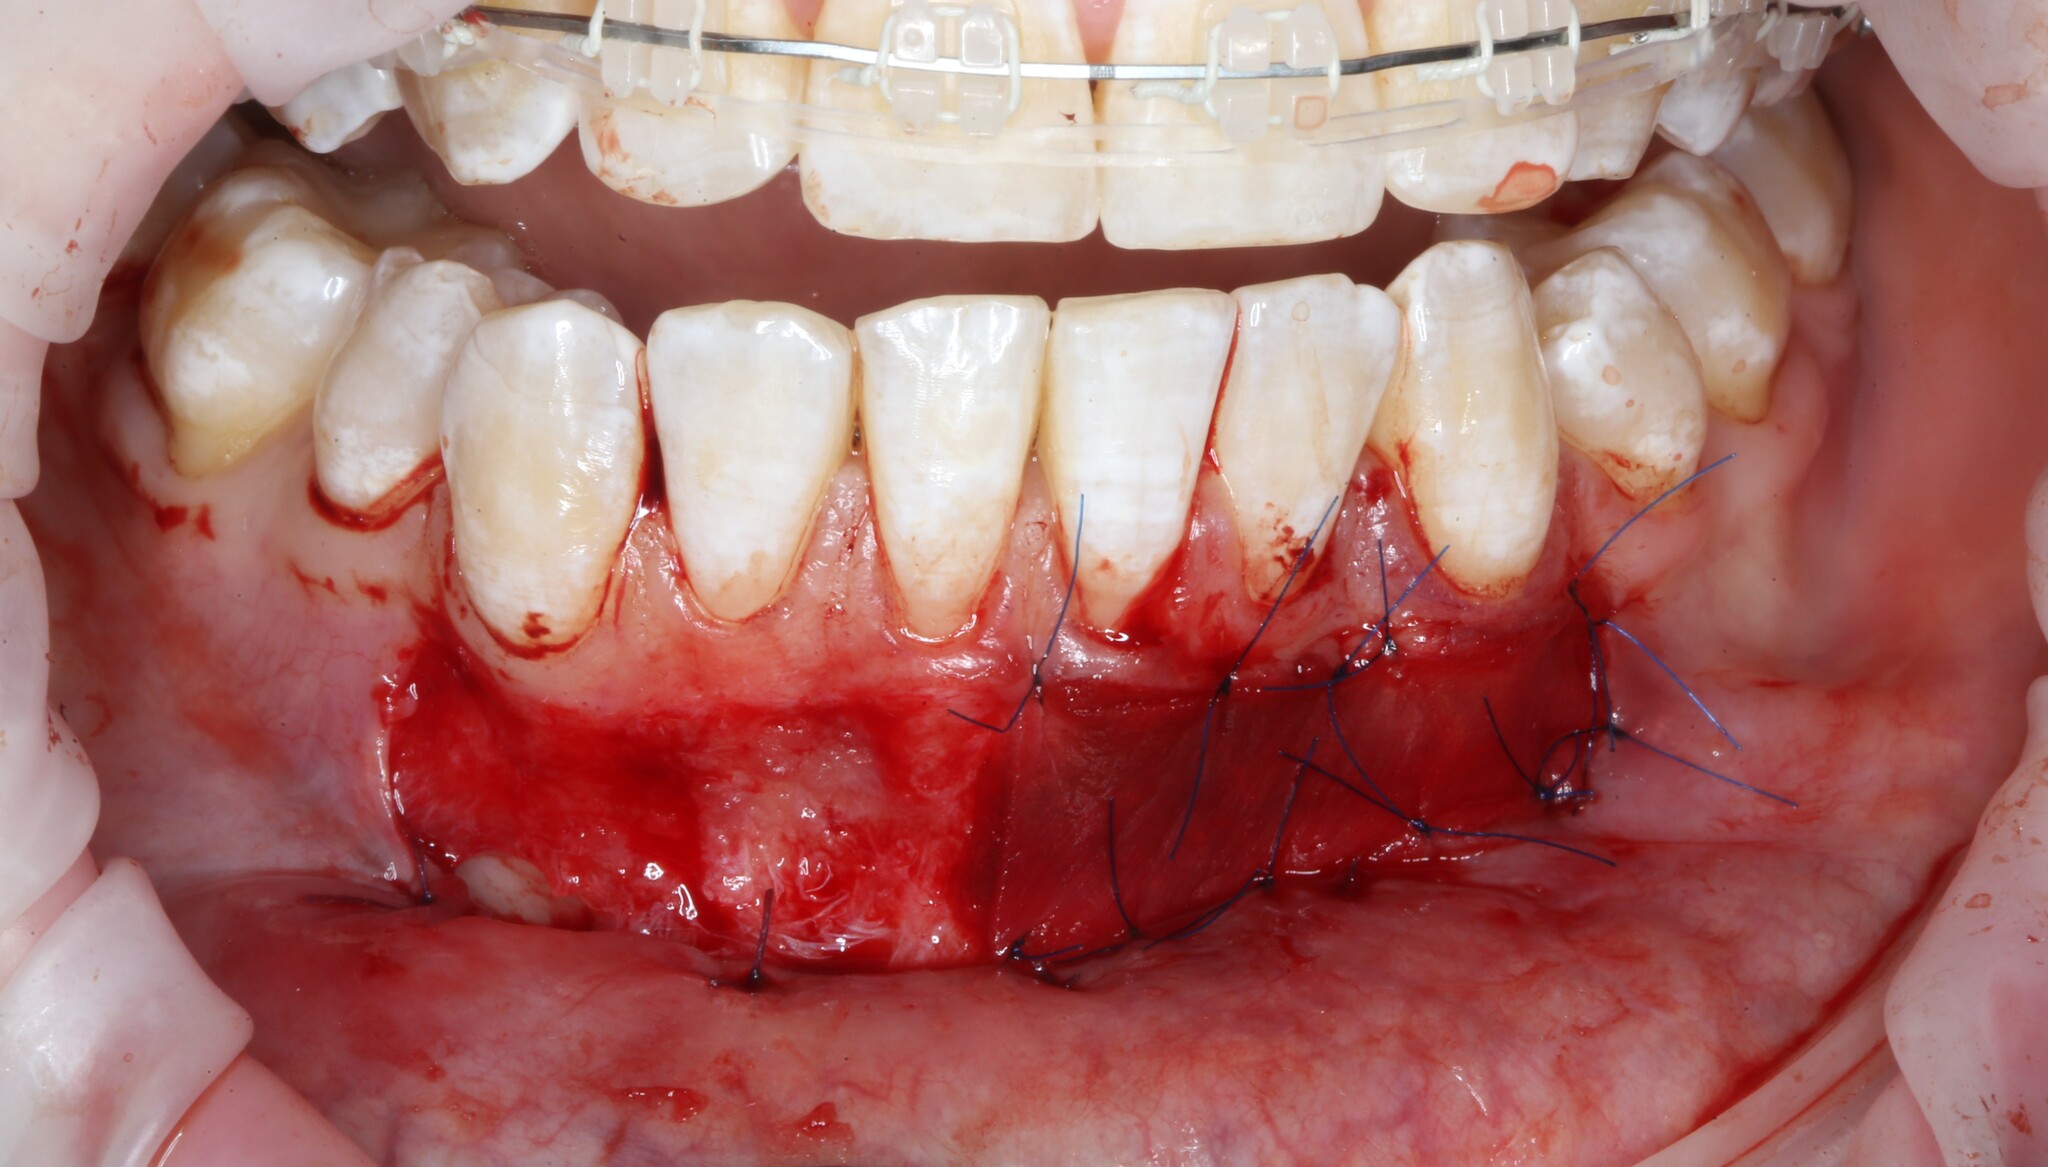

После проведенной анестезии границы слизистых видно отчетливее:

Там, где «вздулось», – подвижная слизистая оболочка, где нет – прикрепленная десна.

Разрез проводится как раз на их границе:

Разрез необходимо делать не до кости, а до надкостницы.

Получив аппетитную картинку для «Ганнибала», необходимо подшить ту часть, которую мы сместили вниз к надкостнице:

Такие швы необходимо наложить в нескольких местах для фиксации слизистой:

Операция закончена – ничего сложного нет: